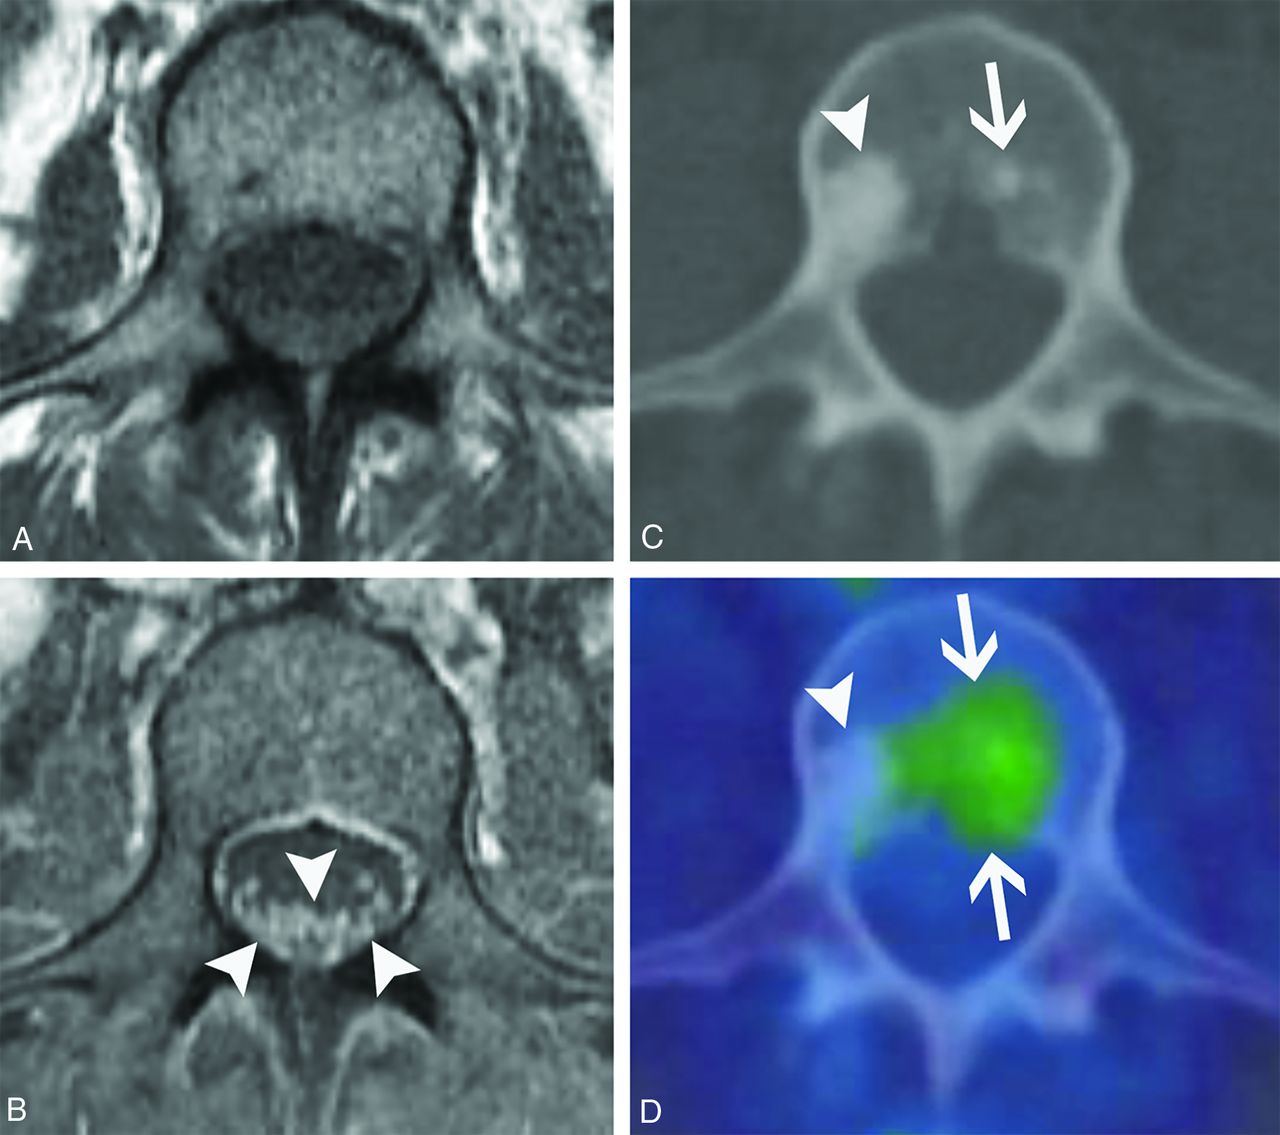

POEMS syndrome. A 50-year-old woman presented with weakness, burning, and tingling in her extremities that had waxed and waned over 4 years. Axial T1-weighted pre- (A) and postcontrast (B) images from her lumbar spine MR imaging show diffuse enlargement and enhancement of the cauda equina nerve roots (B, arrowheads). Axial CT (C) and fused FDG-PET/CT (D) images show a non–FDG-avid lumbar vertebral sclerotic lesion (C and D, arrowheads) and an adjacent mildly FDG-avid sclerotic lesion (C and D, arrows). After additional work-up, she was diagnosed with osteosclerotic multiple myeloma, which is characterized by osteosclerotic lesions with variable FDG avidity. Her MR imaging findings were ultimately attributed to polyneuropathy in the setting of POEMS syndrome.